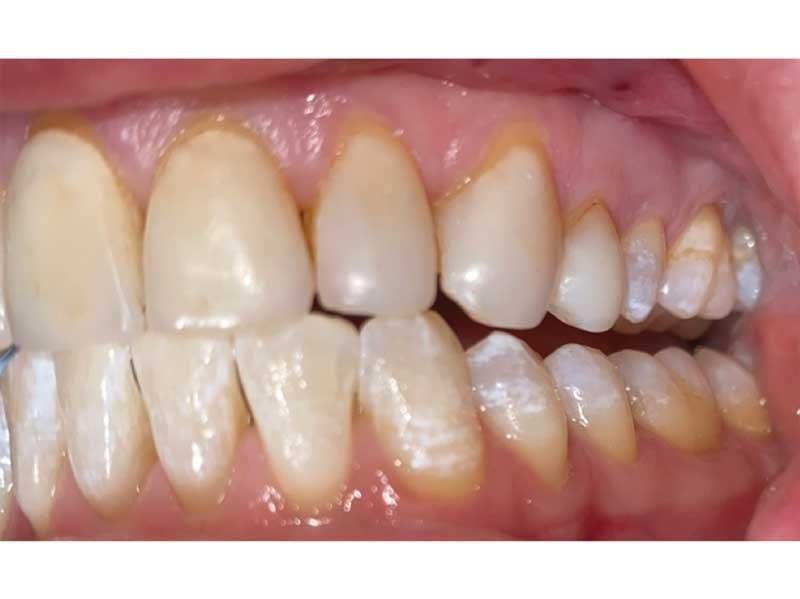

Meet Lorraine, who came into my office to “redo her bonding.” Lorraine had some upper anterior teeth done years ago with resin, which now was dull, stained and breaking down (Figs. 1–3). She had an amount of money in mind that she thought it would cost. She was very wrong.

Fig. 1

Fig. 3